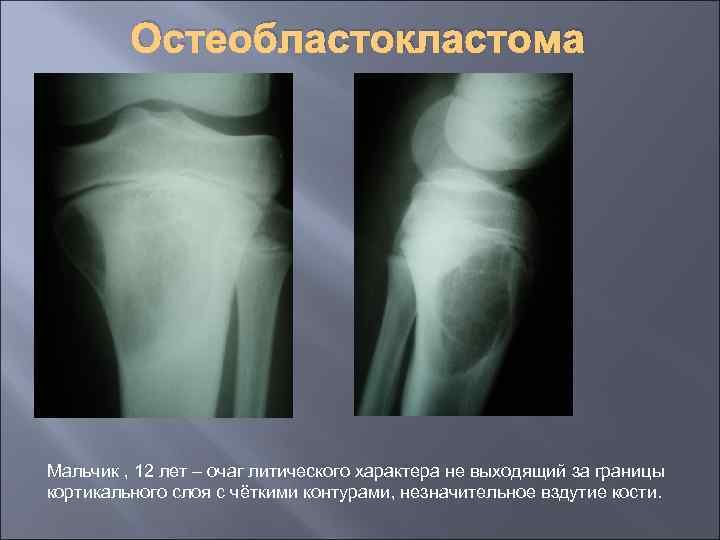

Остеобластокластома Мальчик , 12 лет – очаг литического характера не выходящий за границы кортикального слоя с чёткими контурами, незначительное вздутие кости.